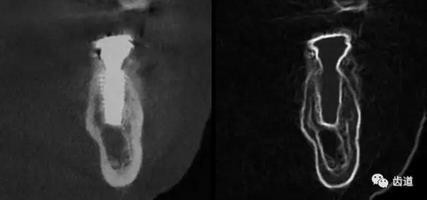

CBCT在牙體牙髓病科治療中,對牙根周圍的解剖關(guān)系、炎癥病變、囊腫等就能夠輕而易舉的進(jìn)行診斷。甚至與牙齒內(nèi)根管的數(shù)目、走向、分支等都能夠通過牙科CT進(jìn)行展示,使臨床醫(yī)生的根管治療不再是完全憑手感的“經(jīng)驗(yàn)科學(xué)”。通過CBCT,還可以對一些“久治不愈“的疑難病例進(jìn)行檢查和診斷,例如根縱列的診斷、根管內(nèi)異物的定位等,找準(zhǔn)了原因,結(jié)合先進(jìn)的治療技術(shù)因病施治,使疑難病例的治療變的輕松起來。

1、牙髓根管治療

1)根管治療中牙膠尖充填在CBCT中的影像

2)根管測量